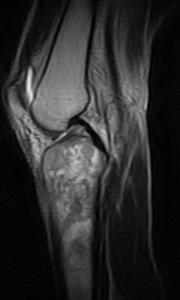

3.jpg

PD脂肪抑制序列

矢状位片

T1加权像

股骨外侧髁前外侧面、胫骨近端及髌骨上极可见异常信号(T1加权像低信号,T2/PD脂肪抑制序列呈不均匀高信号)浸润性病变,伴有边界不清的过渡带。可见少量骨外成分。